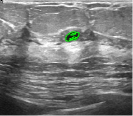

Unlike MR images mentioned above, ultrasound images offer real-time imaging but usually have lower resolution and contrast, making it difficult to differentiate between adjacent tissues and often introducing artifacts and noise that complicate segmentation. However, the RefLSM is robust to high levels of noise and intensity inhomogeneity, regardless of the type of medical image. To validate this, we perform segmentation comparison experiments on breast ultrasound images and calculate the Dice coefficient and Precision values for all models under evaluation.

In Fig. 10, the 1st row displays original images and initial contours for the RefLSM, while the second row shows the RefLSM’s segmentation results. Even with high levels of noise and severe intensity inhomogeneity caused by acoustic shadowing and motion artifacts, our model successfully identifies object edges, achieving an average Precision value of 0.9812. Table 4 shows that the RefLSM requires no more than 10 iterations and has an average processing time of only 1.79 seconds to segment images in Fig. 10.

To further validate the effectiveness of our model, we compared it with the ICTM, RESLS, and ALF models, represented in the 2nd, 3rd, and 4th rows of Fig. 11, respectively. The 5th row displays our proposed model. To better compare the segmentation results, we presented the initial contours in the 1st row, and the ground truth in the 6th row. We can observe that the ALF model struggles with boundary identification and has significant misclassification due to the boundary confusion in ultrasound images commonly caused by overlapping of soft tissues. While the ICTM and RESLS models perform well in some cases like column 1,4, and 7, they still face under-segmentation and over-segmentation problems when images are low contrast or have complex edges like column 1, 3 and 5. In addition to visual comparisons, we calculated the Precision and Dice coefficient for each model, as shown in Table 2. Clearly, the RefLSM outperforms all the other models in terms of mean score. Based on these results, we draw Fig. 12 to present the data distribution and facilitates comparison of different models’ performance across various breast ultrasound images. Although the ICTM model shows relatively close performance, it has nearly double the computational cost of the RefLSM. Therefore,the RefLSM demonstrates excellent segmentation capability and efficiency when processing ultrasound images.